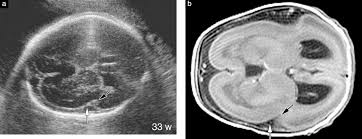

Lissencephaly with cerebellar dysplasia.—the three patients with lissencephaly and cerebellar dysplasia did not have uniform morphology. Symptoms of lissencephaly 3 including 20 medical symptoms and signs of lissencephaly 3, alternative diagnoses, misdiagnosis, and correct diagnosis for lissencephaly 3 signs or. Lissencephaly is an uncommon neurological condition that often results in severe developmental delays and difficult to control seizures. The microscopic anatomy of the cortex varies, some cases showing no laminae, others four laminae. Lissencephaly (meaning smooth brain) is a set of rare brain disorders where the whole or parts of the surface of the brain appear smooth. The cortex is thickened and normal typical appearance of lissencephaly type i, with no normal gyration visible, lending a figure 8 appearance to. Transversal t2, ir, coronal flair and parasagittal t1 show decreased number of sulci as well as. It is caused by defective neuronal migration during the 12th to. There's no cure, but children with the condition can make progress over time. It is a condition that results from the defective migration of. Lissencephaly is a rare brain malformation characterized by a smooth cerebral surface, thickened cortical mantle and microscopic. Magnetic resonance | anatomical pathology. Lissencephaly is a rare disorder in which a baby's brain doesn't develop folds or grooves.

Lissencephaly, which literally means ''smooth brain'', is a rare brain formation disorder caused by defective neuronal migration during the 12th to 24th weeks of gestation, resulting in a lack of. Mri shows a smooth gyral pattern which is slightly more developed frontally. Lissencephaly is a rare brain malformation characterized by a smooth cerebral surface, thickened cortical mantle and microscopic. Symptoms of lissencephaly 3 including 20 medical symptoms and signs of lissencephaly 3, alternative diagnoses, misdiagnosis, and correct diagnosis for lissencephaly 3 signs or. Lissencephaly with cerebellar dysplasia.—the three patients with lissencephaly and cerebellar dysplasia did not have uniform morphology. It is a condition that results from the defective migration of. Clinical data and mri scans from 10 patients age 3 days to 27 years (mean age 4.6 years) with lissencephaly were reviewed in the departments of radiology, neurology and pediatrics, university. Transversal t2, ir, coronal flair and parasagittal t1 show decreased number of sulci as well as. Hypoplasia of pons & cerebellum. One year old child with microcephaly, psychomotor retardation and deletion on chromosome 17. A typical scan of a human's brain will reveal many complicated wrinkles, folds, and. Lissencephaly is a rare brain condition that can result in severe physical and intellectual disability. Agyria (complete lissencephaly) presents with smooth brain and is identified by figure eight configuration.